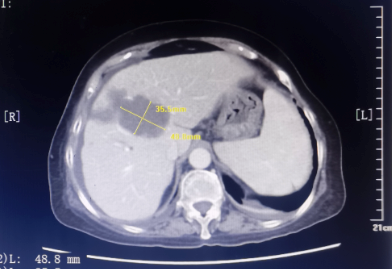

患者为67岁女性,1年余前诊断胃腺癌晚期,肝脏、骨骼及淋巴结多发转移,本次入院复查发现肝脏病灶进展,科主任白俊主任医师、主管医生刘莹主治医师详细分析并与患者家属沟通病情,考虑患者既往接受多线系统性抗肿瘤药物治疗,且治疗过程中多次出现剂量限制性骨髓毒性,继续更换药物治疗的选择空间不多,推荐超声引导下微波消融部分肝脏转移病灶,以期为后续继续免疫及靶向治疗创造在体瘤苗的机会。段宝军副主任医师认真阅片后,考虑该例患者肝转移病灶大(最大径超过5厘米),且毗邻膈肌、肝左静脉及第一肝门等重要结构,因此采用3D可视化手术规划系统设计微波消融方案,在麻醉科常建华副主任医师及手术室的精心配合下,顺利完成了肝转移病灶微波消融手术。

超声引导下肝癌病灶微波消融术微创、经济,且无辐射,是指南推荐的肝癌标准治疗方案。但由于重复进针的人为误差、热传导不足、肝脏储备功能等因素的影响,大肝癌的消融治疗难以做到根治性消融,尤其是危险区域的肝癌病灶微波消融易发生严重并发症,导致超声引导下微波消融的治疗作用与外科手术存在一定差距。